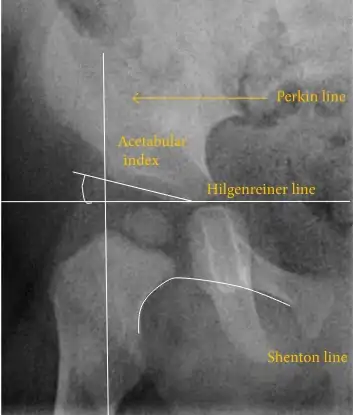

Despite the widespread of ultrasound, pelvis X-ray is still frequently used to diagnose or monitor hip dysplasia or for assessing other congenital conditions or bone tumors.[42] The most useful lines and angles that can be drawn in the pediatric pelvis assessing hip dysplasia are as follows:[42] Different measurements are used in adults.[42]